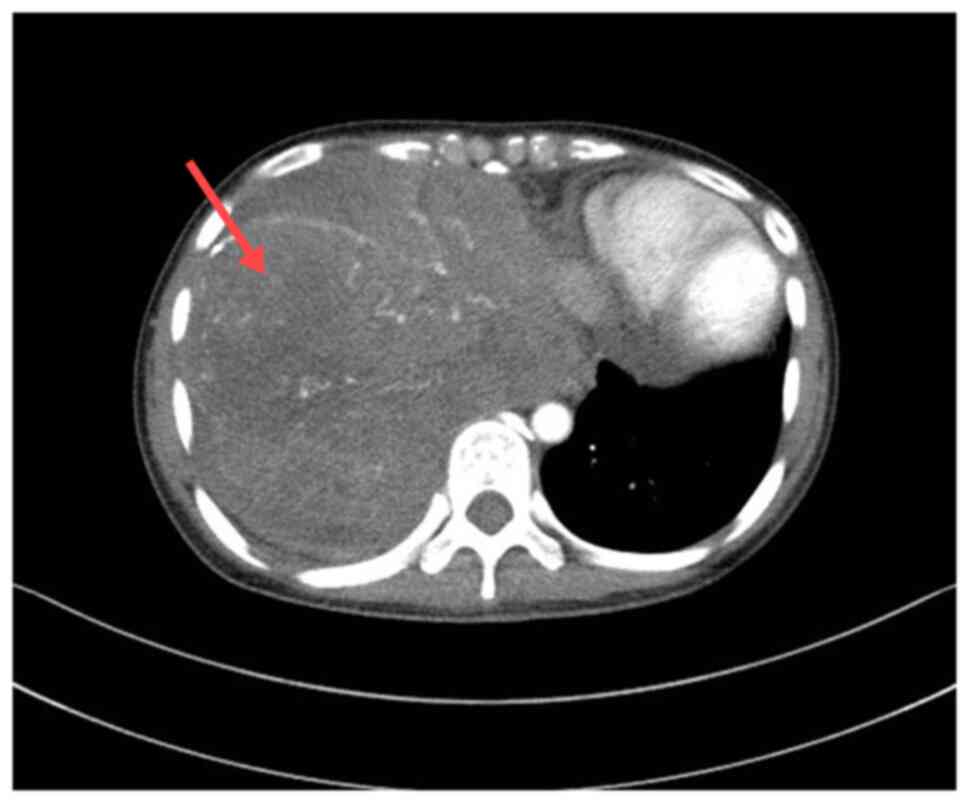

Figure 7.

Computed tomography image at the 5-year follow-up suggesting a right-sided thoracic mass (red arrow).

The patient was in good condition after surgery, and telephone follow-ups were performed at 1, 3 and 5 years after surgery. However, due to personal economic conditions and other factors, the patient declined postoperative radiotherapy and chemotherapy, and regular physical examinations. After 5 years, the patient exhibited symptoms of chest pain and dyspnea. A chest CT scan at the 5-year follow-up visit suggested a recurrence of the thoracic tumor (Fig. 7), and the patient continued to refuse treatment. The patient has been lost to follow-up.